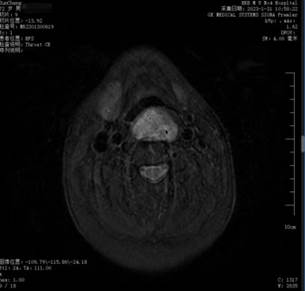

据悉,72岁的孙大爷呼吸困难及吞咽不畅感有近1年的时间,最近两个月加重,严重影响了生活质量。多方诊治无效后,孙大爷来到ac米兰官网中文网站四院行相关检查后,发现口咽至喉咽部长了一个巨大的肿物,MRI显示肿物位于咽后间隙内。

(图1、2核磁检查见口咽至喉咽巨大肿物)